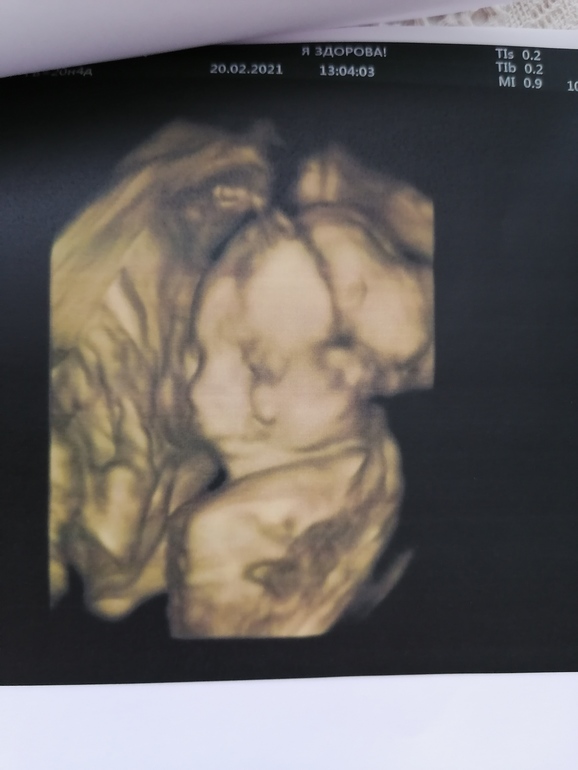

УЗИ прошло шикарно, врач меня вспомнила, все расспросила как и что. Всё рассмотрела идеально. Муж сидел с открытым ртом. Сделали нам аж 15 фото, прям фотосессия была у сыночка🥰😉. Он так мило зевал, язычком водичку ловил💙💙💙. Прям умиление сплошное🥰. Лежит головой вниз.

По УЗИ все отлично, только вот по узи животик в четверг был больше чем сегодня, но это погрешности узи🙈😂. Вес 400гр.

Ну и наши фоточки🥰👶🙏🙏🙏.

Ну и фотосессия сыночка👶🙏🙏🙏🥰.